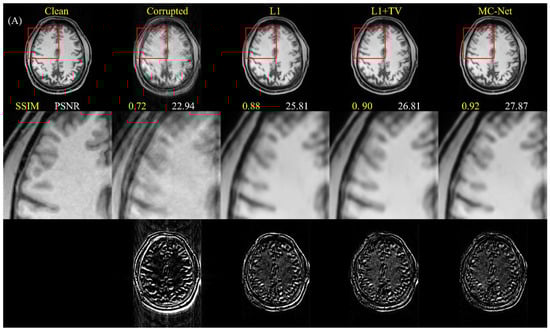

4.1. Quantitative Improvements for Motion-Corrupted Images

5.1. Advantages of Two-Stage Training and Multiple-Loss Function